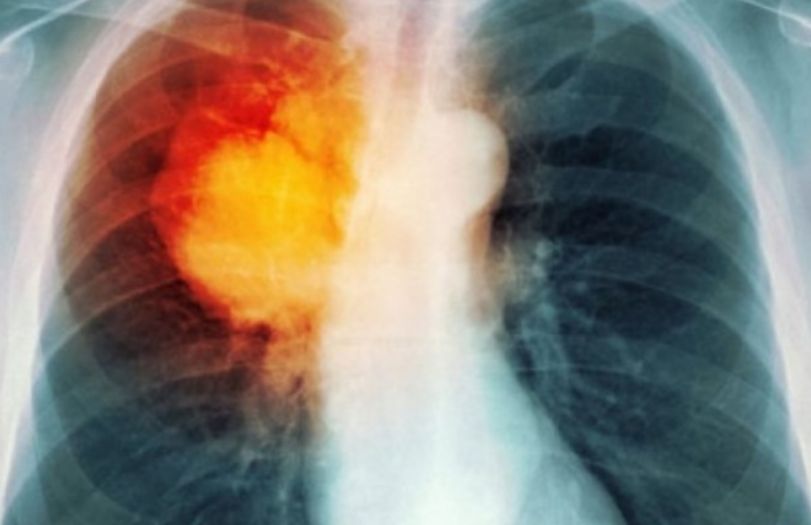

SPOK është termi që përfshin disa sëmundje të rënda të mushkërive, si bronkiti kronik, emfizema dhe gjendje të tjera që vështirësojnë funksionimin e mushkërive. Përveç duhanpirjes, faktorë të tjerë si ndotja e ajrit dhe gjenetika mund të kontribuojnë në zhvillimin e kësaj sëmundjeje.

Gratë janë më të rrezikuara se burrat që të kenë përkeqësim të gjendjes si pasojë e infeksioneve ose ekspozimit ndaj ndotësve të ajrit.